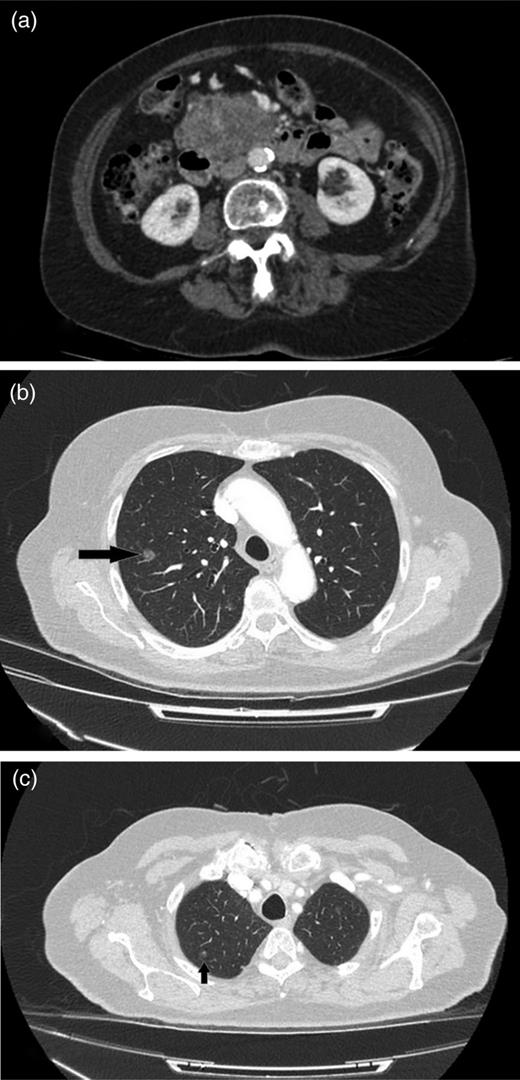

CT shows cystic mass in the uncinate process of pancreas measuring 4 cm in 2008.